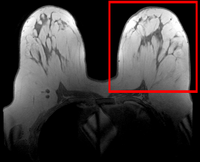

Slicer Registration Use Case Exampe #6: Breast MRI Treatment Assessment

We seek to align the post-treatment (PostRx) scan with the pre-treatment scan to compare local effects (left side only).

Registration Results